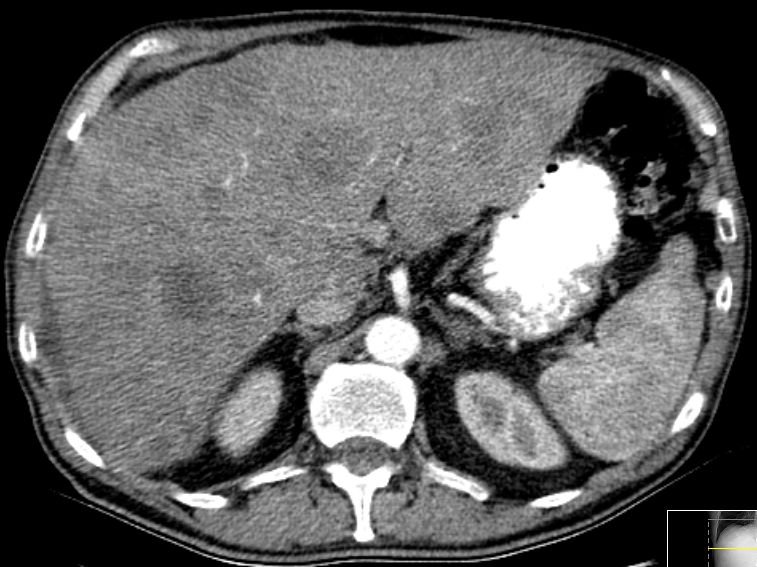

67-jähriger Mann mit primär pulmonal und hepatisch metastasiertem Tumor der rechten Colon-Flexur. Im Nativ-CT Metastasen undeutlich.

CT Kontrastmittel arterielle Phase: Metastasen deutlich.

CT Kontrastmittel venöse Phase: Metastasen sehr deutlich.